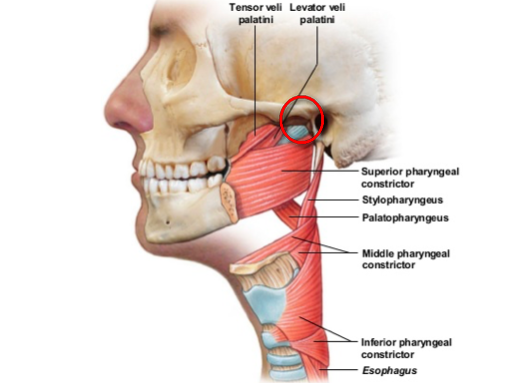

Der weiche Gaumen ist Teil des Mundhöhlendaches und die Fortsetzung des harten Gaumens. Er besteht aus der Uvula (dem sogenannten Zäpfchen) und dem Gaumensegel (Velum palatini). Um das Gaumensegel liegen drei kleine Muskeln. Zwei davon, nämlich der Muskulus tensor veli palatini und der Muskulus levator veli palatini, werden später nochmals gesondert erwähnt – also merken! Der gesamte weiche Gaumen spielt eine maßgebliche Rolle beim Druckausgleich, da er die Mundhöhle mit der Nasenhöhle verbindet.

Da hierbei die beiden kleinen Muskeln (Tensor und Levator veli palatini) stark involviert sind, machen wir uns zunächst die anatomische Lage dieser Muskeln klar. Der Musculus levator veli palatini kommt vom Felsenbein (der Knochen hinter dem Ohr) und setzt am weichen Gaumen an, den er bei Anspannung nach hinten oben bewegt. Dabei nimmt er den Eingang der Tube mit, der sich dabei öffnet. Der Musculus tensor levi palatini kommt auch von einem Schädelknochen, dem sogenannten Keilbein und setzt am weichen Gaumen an. Wenn er in Aktion tritt, spannt er den weichen Gaumen an und versteift dabei die vordere seitliche Wand der Tube, die dadurch in geöffnetem Zustand bleibt.

Diese Technik wurde nach dem britischen HNO-Arzt Joseph Toynbee benannt (1815 – 1866). Er fand heraus, dass die Muskeln tensor und levator veli palatini beim Schluckakt die Tube öffnen. Bei manchen Tauchern gelingt er Druckausgleich rein durch Schlucken.

Zu 3.) Pure

Mit ein bisschen Übung kann man lernen die für die Tubenöffnung verantwortlichen Muskeln bewusst anzusteuern. Das kann man durch willentliche Anspannung der Muskulatur um das Kiefergelenk und des weichen Gaumens ausprobieren. Ihr könnt auch die Kehlkopfmuskeln zu Hilfe nehmen. Das muss man ausprobieren. Bei erfolgreicher Anspannung unserer zwei kleinen Tuben-Hilfsmuskeln spürt ihr eine Druckveränderung im Mittelohr und wisst, dass es funktioniert hat.